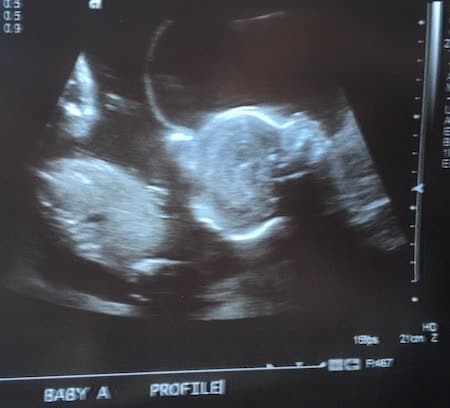

Ultrasound Photos at 22 Weeks Pregnant With Twins